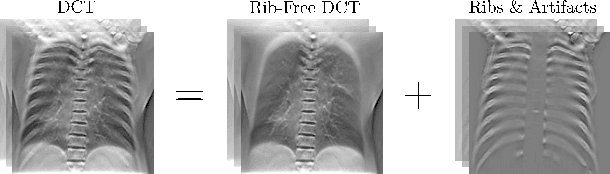

Abstract:Digital chest tomosynthesis (DCT) is a technique to produce sectional 3D images of a human chest for pulmonary disease screening, with 2D X-ray projections taken within an extremely limited range of angles. However, under the limited angle scenario, DCT contains strong artifacts caused by the presence of ribs, jamming the imaging quality of the lung area. Recently, great progress has been achieved for rib suppression in a single X-ray image, to reveal a clearer lung texture. We firstly extend the rib suppression problem to the 3D case at the software level. We propose a $\textbf{T}$omosynthesis $\textbf{RI}$b Su$\textbf{P}$pression and $\textbf{L}$ung $\textbf{E}$nhancement $\textbf{Net}$work (TRIPLE-Net) to model the 3D rib component and provide a rib-free DCT. TRIPLE-Net takes the advantages from both 2D and 3D domains, which model the ribs in DCT with the exact FBP procedure and 3D depth information, respectively. The experiments on simulated datasets and clinical data have shown the effectiveness of TRIPLE-Net to preserve lung details as well as improve the imaging quality of pulmonary diseases. Finally, an expert user study confirms our findings.